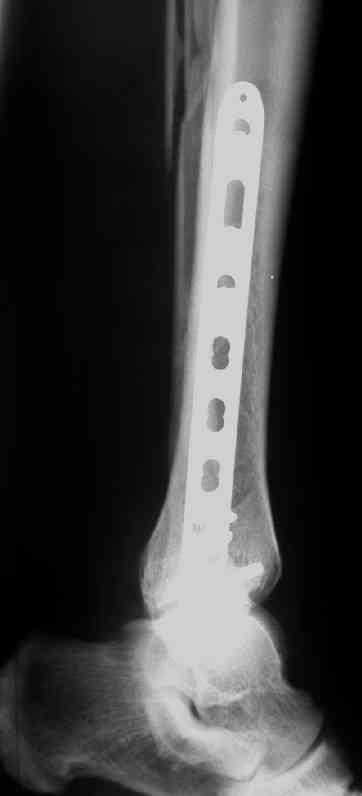

Выполнил MIPO предизогнутой метафизарной LCP

Красиво получилось, поздравляю. Насчет немедленной полной нагрузки, как на гвозде, про что Алексей Семенистый говорит - будете разрешать сразу?

И все же немного критики:1) Вы добивались анатомичной репозиции, которая требует абсолютной стабильности, которая в свою очередь возможноа только в условиях межфрагментарной компрессии. Пластина уложена как мостовидная, не хватает стягивающнго винта. 2) есть укорочение малоберцовой кости, необхордимо восстановить ее длину! В таком виде я бы не стал разрешать раннюю нагрузку. Добавить самую малость: стягивающий винт и остеосинтез малоберцовой кости и больной может наступать сразу.

В этом случае остеосинтез выполнялся малоинвазивно и я не добивался абсолютной стабильности преднамеренно. Стабильность относительная и ст. её зависит от механических свойств импланта;возможно, нужно было взять длиннее пластину, увеличив её рабочую длину

Все справедливо для оскольчатого перелома, когда вы не добиваетесь анатомичной репозиции. При простом переломе адекватной будет анатомичная репозиция, и она у Вас получилась закрыто. Если Вы изначально предполагали относительную стабильность, то штифт позволил бы более раннюю и агрессивную реабилитацию

В последствии стал выполнять мостовидную фиксацию не только при оскольчатых переломах, но и при простых, прооперировал около 30 голеней, сращение наступило у всех периостальной мозолью.